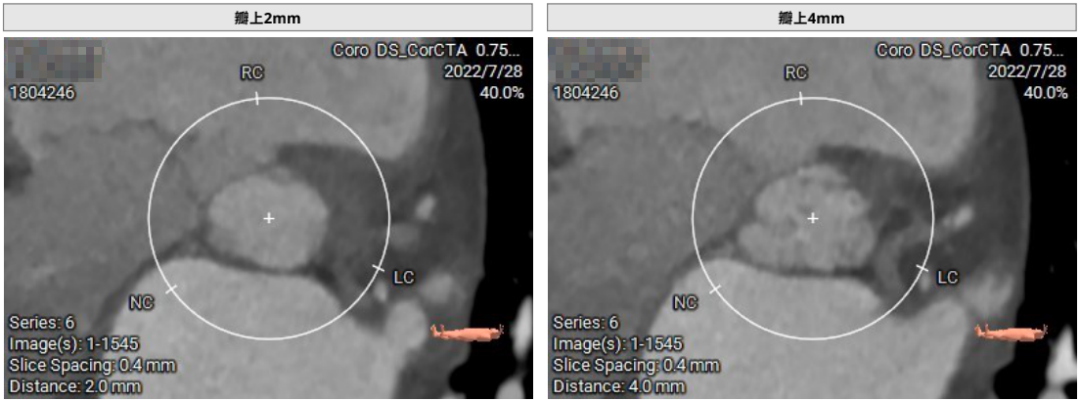

患者71岁女性,诊断为主动脉瓣重度狭窄合并心功能不全,瓣口面积仅0.5cm²,跨瓣压差超过50mmHg,且EF仅27%,心功能极差。术前CT检查瓣环周长72.2mm,LVOT呈喇叭型。CT检查同时发现患者入路血管狭窄,股动脉直径5.3cm,锁骨下和颈内动脉直径都小于5.0cm,对操作造成了一定困难。

首先,术前要求全员参加讨论分析,明确手术难点和应对策略。其次,临时起搏器常规通过颈内静脉放置漂浮导管,能有效避免心脏穿孔,且总体来讲起搏器植入成功率高,并发症更少。再次,为了避免入路血管并发症,CT检查后,术中应再通过左股动脉穿刺造影,“双重保险”确定入路血管的条件;对于术前评估冠脉风险大的患者,术中也要通过冠脉造影再次测定瓣环到冠脉开口的距离,重复评估冠脉风险。最后,始终坚持把外周所有鞘管都缝在皮肤上,可以有效避免鞘管移动带来的并发症。